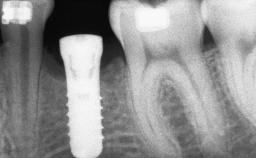

Replacement of Multiple Teeth in a Partially Dentate Posterior Mandible with a Fixed Dental Prosthesis Using a Flapless Approach

An 80-year-old female patient was referred to clinic for rehabilitation of her dentition. The patient’s medical history revealed no significant findings that would preclude routine dental and oral surgical procedures. She reported no drug allergies and was currently taking no prescription medications.

Her chief complaint was her inability to masticate efficiently due to the recent loss of her mandibular second premolars and first molars bilaterally. She expressed a desire for fixed prostheses in the shortest possible time due to her advanced age, requesting that replacement teeth should look as natural as possible. She was otherwise comfortable and not experiencing any symptoms from her teeth.